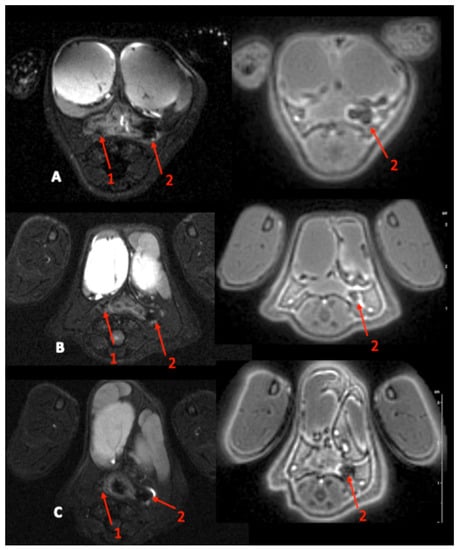

- day 35, baseline MRI: after maintaining the threads for 28 days, 2 inflammatory fistulas were obtained (Figure 6A) and a perineal MRI was performed to assess the pre-treatment tracts.

| Fistula tract diameter (mm) | 2.17 ± 0.6 [1.2–3.3] | 1.92 ± 0.3 [1.5–2.5] |

| - T2 Signal (a.u) | 3.60 ± 0.56 | 3.50 ± 0.52 |

| [2.22–4.56] | [2.13–4.61] | |

| - ADC (mm2/s) | 1.42 ± 0.20 | 1.49 ± 0.23 |

| [1.058–1.709] | [1.09–1.92] | |